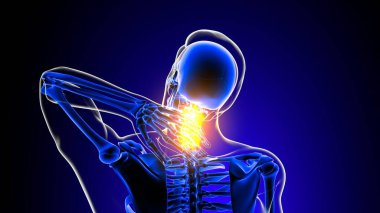

İnsan iskeleti anatomisi Scapula Kemiği Tıbbi Konsept için 3D Hazırlama

İskeletanatomiçene kemiğiyarım ayboyunlomberetmoidcapitateAltkısmınıHamate3d oluşturmaGöğüs kafesi3B illüstrasyoncarpalsağız sapımetakarplaralın kemiğiApendiküleruyluk kemiğioksipital kemikBurun kemiğikemiğigöğüs kemiğinin gövdesiayak kemikleriyarıçap kemiğiparietal kemikeksenel iskeletKalça kemiğilacrimal bonepalatine boneproximal phalangesinferior nasal conchaintermediate phalangesdistal phalangesclavicle bonekaval kemiğiBurun kıkırdağıkol kemiğikürek kemiğiBenzer İçerikler